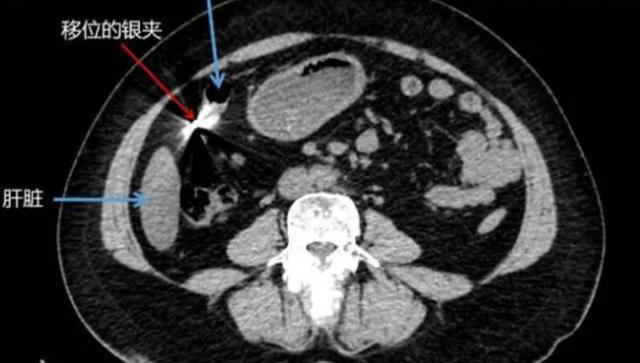

11月3日,东莞市的街头,李女士不慎与一辆小车相撞,随后被120急救车紧急送往医院。在医院进行的检查中,医生却发现了令人震惊的情况,李女士患有肠穿孔、腹膜炎以及感染性休克,她的病情相当严重。但令人不解的是,一名在车祸后遭受如此严重伤害的患者体内竟然隐藏了一枚0.8厘米长的金属异物,其质地坚硬,酷似金属结扎夹。

在医生的进一步询问中,李女士回忆起了自己20年前曾进行过的结扎手术,这一信息成为医生推断金属异物来源的重要线索。医生认为,这枚金属异物很可能是手术中使用的金属结扎夹的残留物,脱落后滞留在她的体内。因此,医生提出了一个令人深思的建议,那就是那些接受金属结扎手术的患者应定期进行拍片检查,以确保金属结扎夹没有脱落或移位,从而降低患者潜在的健康风险。